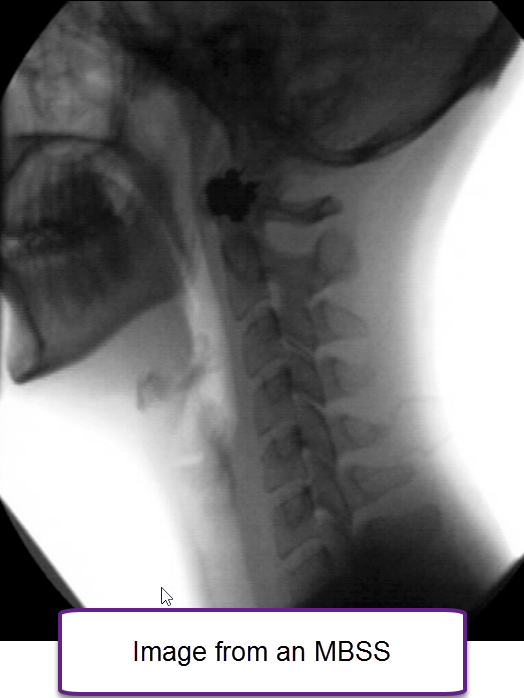

Barium swallow study, lateral view showing laryngeal aspiration, an Radiology Barium Swallow Near Me the fluoroscopy department of st james's hospital carries out the full range of fluoroscopic guided procedures including. barium swallow | st. learn what a barium swallow/meal is, why your doctor may refer you for it, how to prepare, and what to expect during the. barium swallow is a test of the pharynx, esophagus, and proximal stomach. Radiology Barium Swallow Near Me.